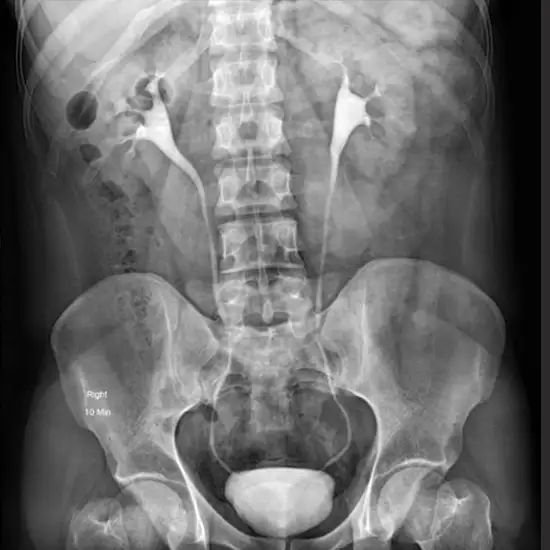

An intravenous pyelogram (PIE-uh-low-gram), also known as an excretory urogram, is a urinary tract X-ray. Your doctor can see your kidneys, bladder, and the tubes that carry urine from your kidneys to your bladder during an intravenous pyelogram (ureters).

An intravenous pyelogram is a test that looks at your kidneys, ureters, and bladder. It allows your doctor to assess the size and shape of these structures as well as their functionality.

You lie on your back on an exam table for an intravenous pyelogram. The X-ray machine is usually attached to or built into the table. An X-ray image intensifier — the machine component that produces the images — is placed over your abdomen. After you've settled into a comfortable position on the table, the exam proceeds as follows:

Before any dye is injected, X-rays of your urinary tract are taken.

• An X-ray dye is injected into your IV line.

• As the dye flows through your kidneys, ureters, and bladder, X-ray images are taken at regular intervals.

• You may be asked to urinate again near the end of the exam.

• You then return to the exam table to allow the medical team to obtain X-ray images of your empty bladder.